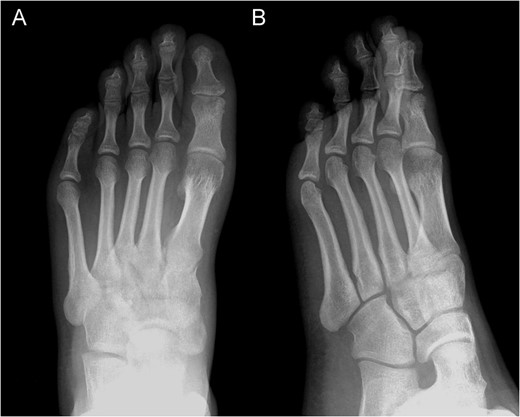

Posterior–anterior X-ray imaging of the left forefoot, showing an intra-articular osteolytic lesion (arrow) in the condyle of the proximal phalanx of the hallux.

Posterior–anterior (A) and oblique (B) X-ray imaging of the left forefoot, showing the integration of the bone graft after 6 weeks.